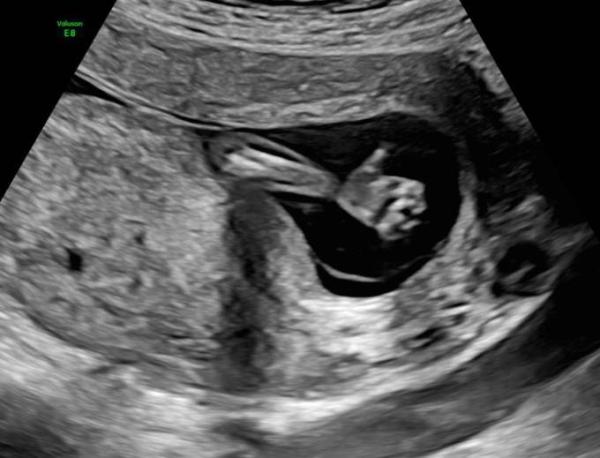

Wir bekommen ein Mädchen

WIr sind so happy. Wir haben schon 3 tolle Jungs und nun gesellt sich noch ein Mädchen dazu (:

alles ist gut. es dürfte 166g schwer sien und 16 cm groß. zumindest wenn ich das richtig rausgelesen habe

Sie hat sich bewegt und uns ein Daumen hoch gegeben. Ich bin sehr erleichtert das alles ok ist. Mein Mann war auch wieder mit dabei. (:

Das ist ja ein tolles Ultraschallbild. So niedlich die kleine Hand. Schön, dass mit eurer kleinen Maus alles gut ist.